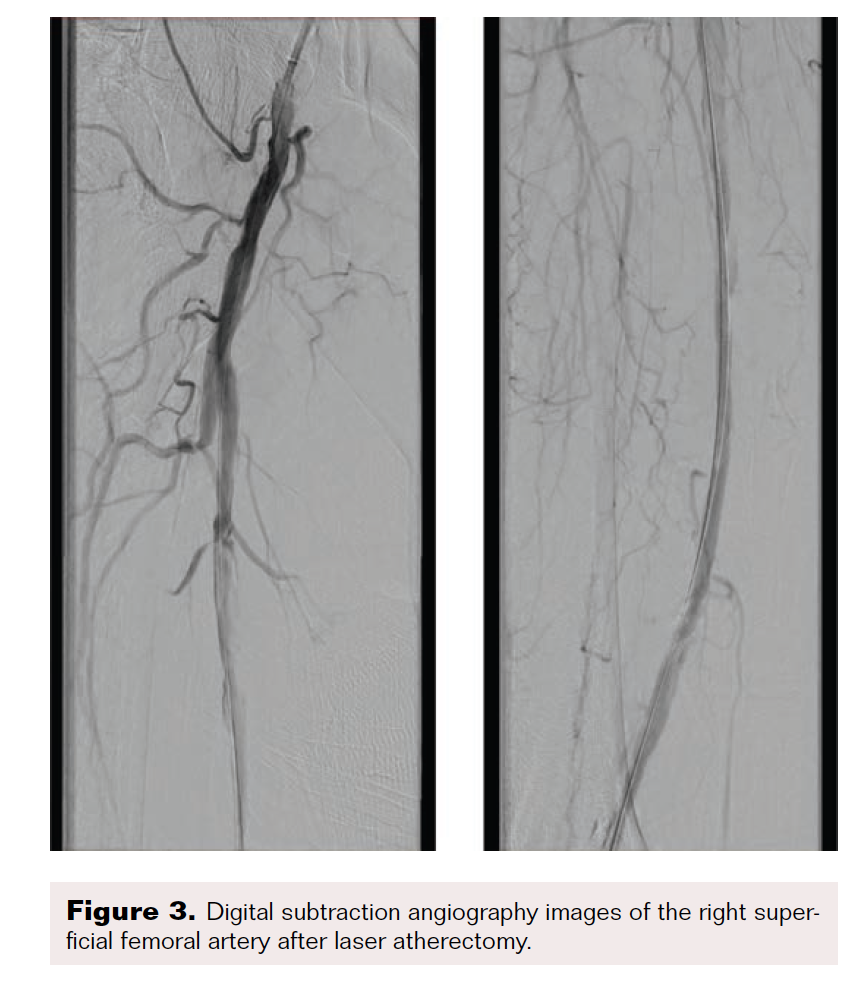

Maintaining an intraluminal course throughout, the SFA and popliteal arteries were successfully traversed using a stiff-angled Glidewire inside of a 0.035" Crosswalk braided peripheral microcatheter (Asahi Intecc Medical) for additional support. After advancing the microcatheter to the distal popliteal artery, the Glidewire was exchanged for a 0.014" pre-curved Mongo ES wire (Asahi Intecc Medical). The occluded anterior tibial artery was successfully navigated with the Mongo wire, after which intravascular ultrasound was performed from the anterior tibial artery proximally to the SFA. Next, laser atherectomy of the SFA, popliteal, and anterior tibial arteries was performed with a 1.7 mm Turbo-Elite laser atherectomy catheter (Philips) (Figure 3 and Figure 4). Following atherectomy, the anterior tibial artery was dilated with an Ultraverse 3.5 x 100 mm balloon (Bard). In preparation for percutaneous transluminal angioplasty of the SFA and popliteal arteries, the Mongo 0.014" wire was exchanged for a 0.035" stiff-angled Glidewire.